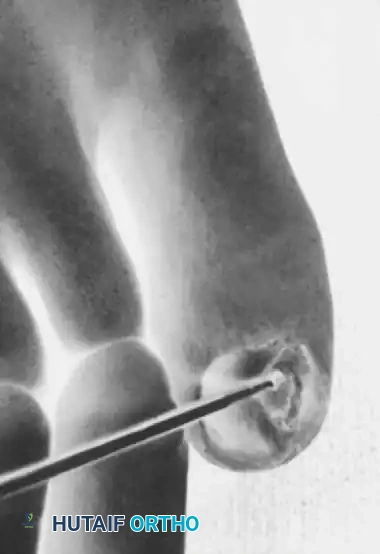

Fig. 84-26B: A small osteotome is directed parallel to the distal phalanx to resect the exostosis at its base.

- Nail Elevation: Carefully dislodge part of the remaining nail from its proximal attachments at the larger side of the exostosis. Leave the remainder of the nail in place. This maneuver fully exposes the exostosis abutting and penetrating the nail bed.

- Osteotomy: Make a small osteotomy paralleling the dorsal cortex of the distal phalanx to remove the exostosis in one piece.

- Contouring: Use a fine rongeur or a high-speed burr to produce a smooth cortical surface, ensuring the removal of any residual osteochondroma tissue or cartilaginous cap.